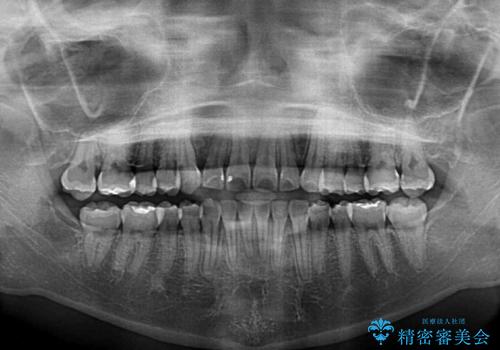

- 前歯のでこぼこと乳歯が残るほどの八重歯を気にして来院された患者様です。

非抜歯にてワイヤー矯正にて治療することとしました。(ただし、親知らずと乳歯は抜歯)

犬歯は歯根が太く長いため、移動には時間を要します。しかし、犬歯は機能面から考えて残すことを選択したいため、長期間をかけて治療を行うこととしました。

治療の度に歯列が改善していったため、長期間の治療も楽しく過ごしていいただき、満足のいく仕上がりとなりました。